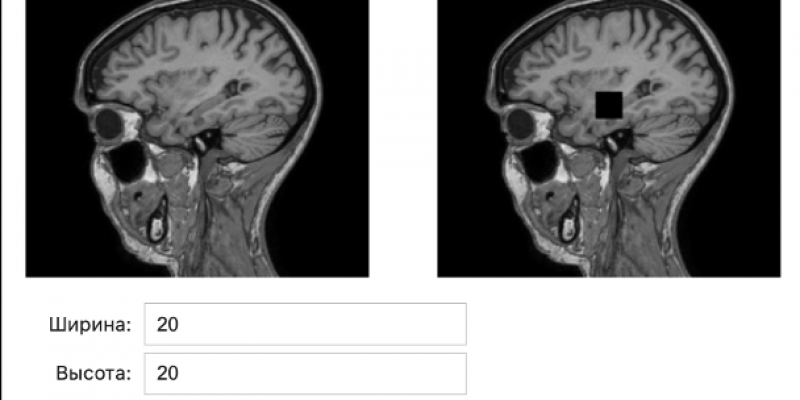

Для решения этой проблемы политеховцы разработали программный прототип, основу которого составили генеративные нейронные сети, их обучают на реальных медицинских изображениях, и затем они создают новые синтетические МРТ-снимки. Специалисты из Самарского государственного медицинского университета предоставили нашим студентам необходимые данные для работы над проектом – последовательные двумерные срезы головного мозга.

Существующие зарубежные аналоги представляют собой закрытые или узкоспециализированные решения. Уникальность политеховской платформы – в сочетании генерации и автоматической проверки качества и структурной согласованности полученных изображений с использованием вычислительных и нейросетевых метрик. Пользователь может управлять процессом генерации, получать готовые данные и использовать их для обучения и тестирования других ИИ-моделей в области анализа медицинских изображений.